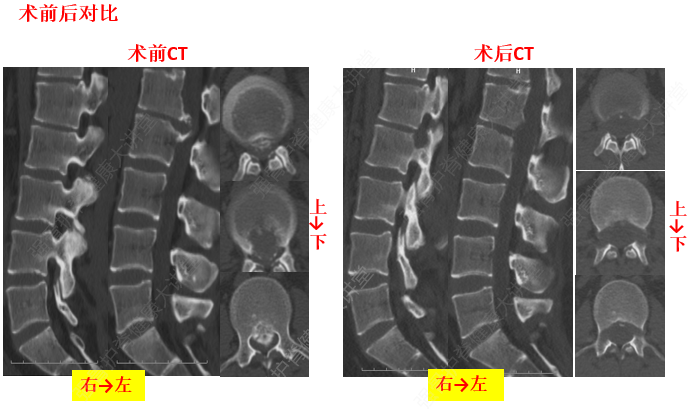

由于頸椎關節突間關節面近乎水平位,一旦椎間盤發生退變、椎間隙即變窄,關節囊及韌帶松弛,加上頸部活動時重力的影響,即可造成積累性損傷,加速頸椎退變和不穩,導致頸椎關節發生移位,使椎間孔變狹,椎管徑發生改變,壓迫神經根或脊髓,產生臨床癥狀與體征。